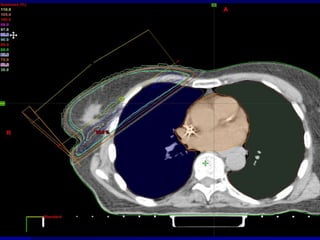

Image-based Conformal Radiation Therapy: 60 Gy62 Gy50 Gy20 Gy45 GyaxialsagittalLeft Breast

Image-based Conformal RadiationTherapy: 60 Gy62 Gy50 Gy20 Gy45 GyaxialsagittalLeft Breast